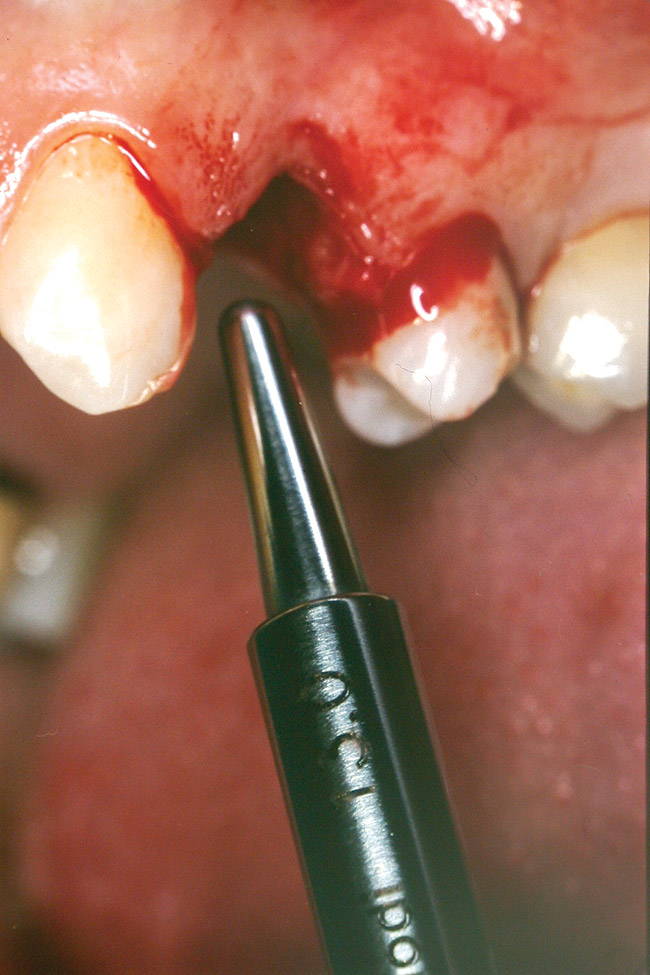

At the time of surgery, the tooth was extracted without harvesting any mucosal flap because the implant site was prepared by means of a pilot drill bur (Figure 13) and alternating osteotomes (Figure 14A and Figure 14B). The implant was positioned and showed primary stability. The implant was loaded 2 days after surgery. Then, splinted PFM crowns supported by custom gold abutments were delivered. At 6 months posttreatment, the radiograph revealed no bone resorption and the clinical result was optimal (Figure 15A and Figure 15B).

Figure 13 The drill bur was used to start the implant site preparation.

Figure 14A and Figure 14B Alternating osteotomes were used to prepare the implant site.